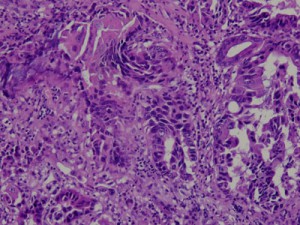

腫瘤の他、胃と十二指腸の粘膜をそれぞれ5〜6カ所サンプリングし病理組織検査を行った所、胃腺癌と診断されました。